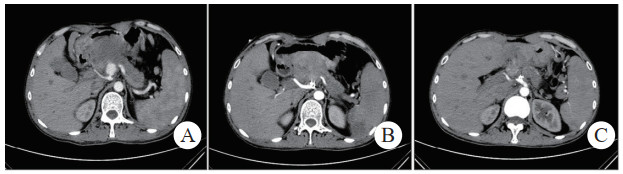

治疗后随诊复查CT显示,患者载瘤动脉及瘤腔内可见栓塞弹簧圈,血肿、假性动脉瘤瘤体体积明显缩小,未见血管再通与假性动脉瘤破裂,见图 2(病例2)。

| 注:图 2病例2 A为患者术前CT增强扫描,示胰腺炎影像,腹腔内见一血肿影,脾动脉起始段可见一瘤样扩张,内见对比剂填充;B、C分别为患者术后3 d及术后1个月复查CT增强示,血肿较前减小,原瘤样扩张处可见弹簧圈影及未见对比剂外溢 图 2 病例2术前、术后CT平扫及增强 |